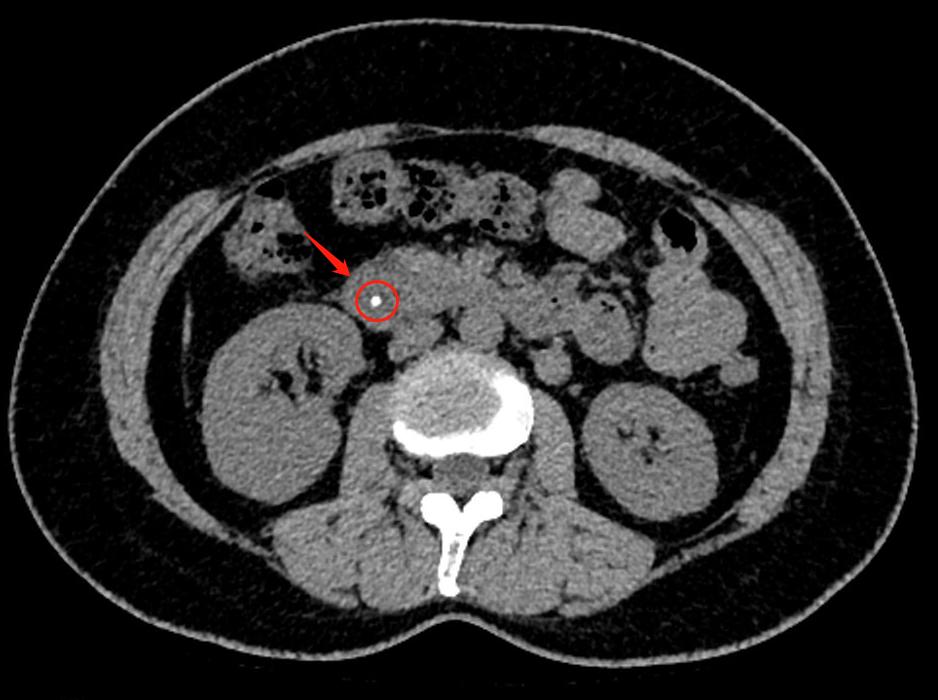

经过了CT检查,很快就找出了原因——胆总管卡着一颗大小约4mm的“石头”。这个石头卡在胆汁与胰液的出口处,让程女士出现腹痛。

程女士的CT片子